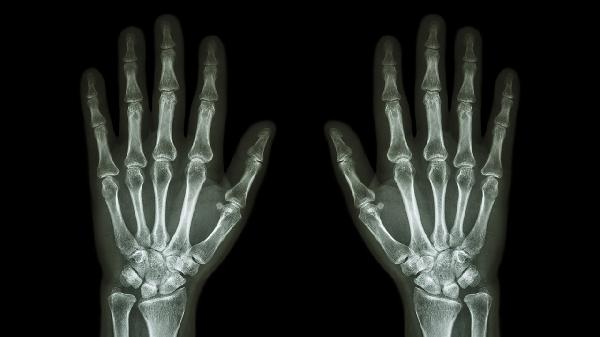

退行性关节病变常见于中老年人,晨起关节僵硬明显,X线可见骨赘形成。可能与年龄增长、肥胖等因素有关,通常表现为关节肿大和活动弹响。遵医嘱使用硫酸氨基葡萄糖胶囊、双醋瑞因胶囊等软骨保护剂,配合关节腔注射玻璃酸钠。